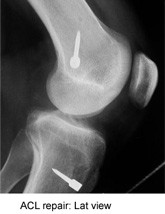

An ACL repair

ACL repair: Lat view